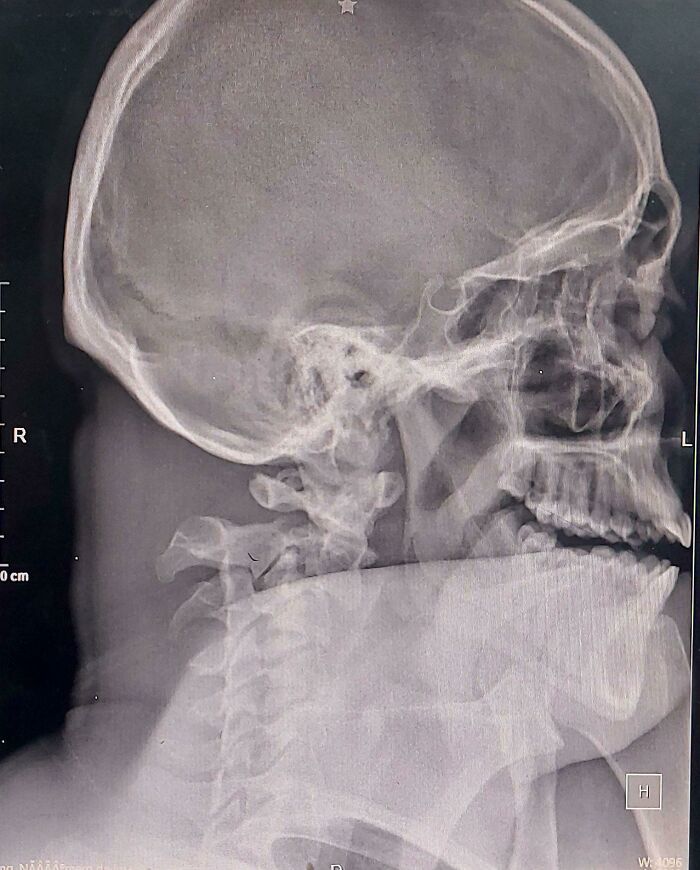

З такою шиєю чоловік приїхав сам на таксі до лікарні

Навіть не професіонал зрозуміє, що шия у чоловіка зовсім не впорядку.